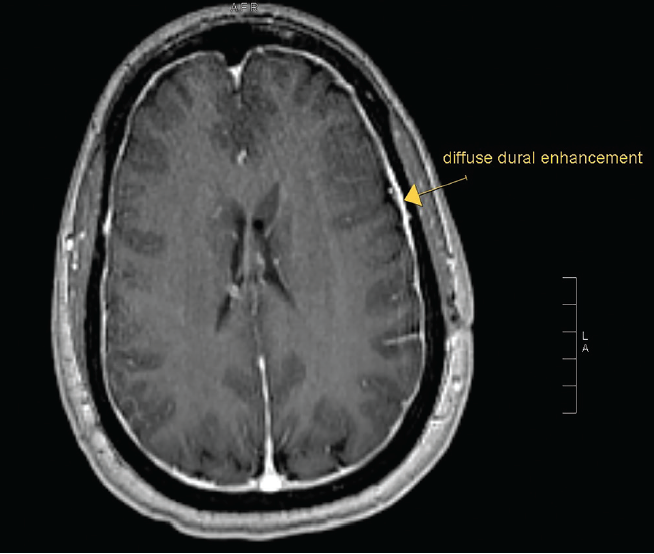

Emily Maxwell; Jason Ramirez, MD; Richard Chang, MD

A 39-year-old woman with a past medical history of idiopathic intracranial hypertension (IIH) presented with worsening headache, nausea, vomiting, and blurry vision.

07/05/2016